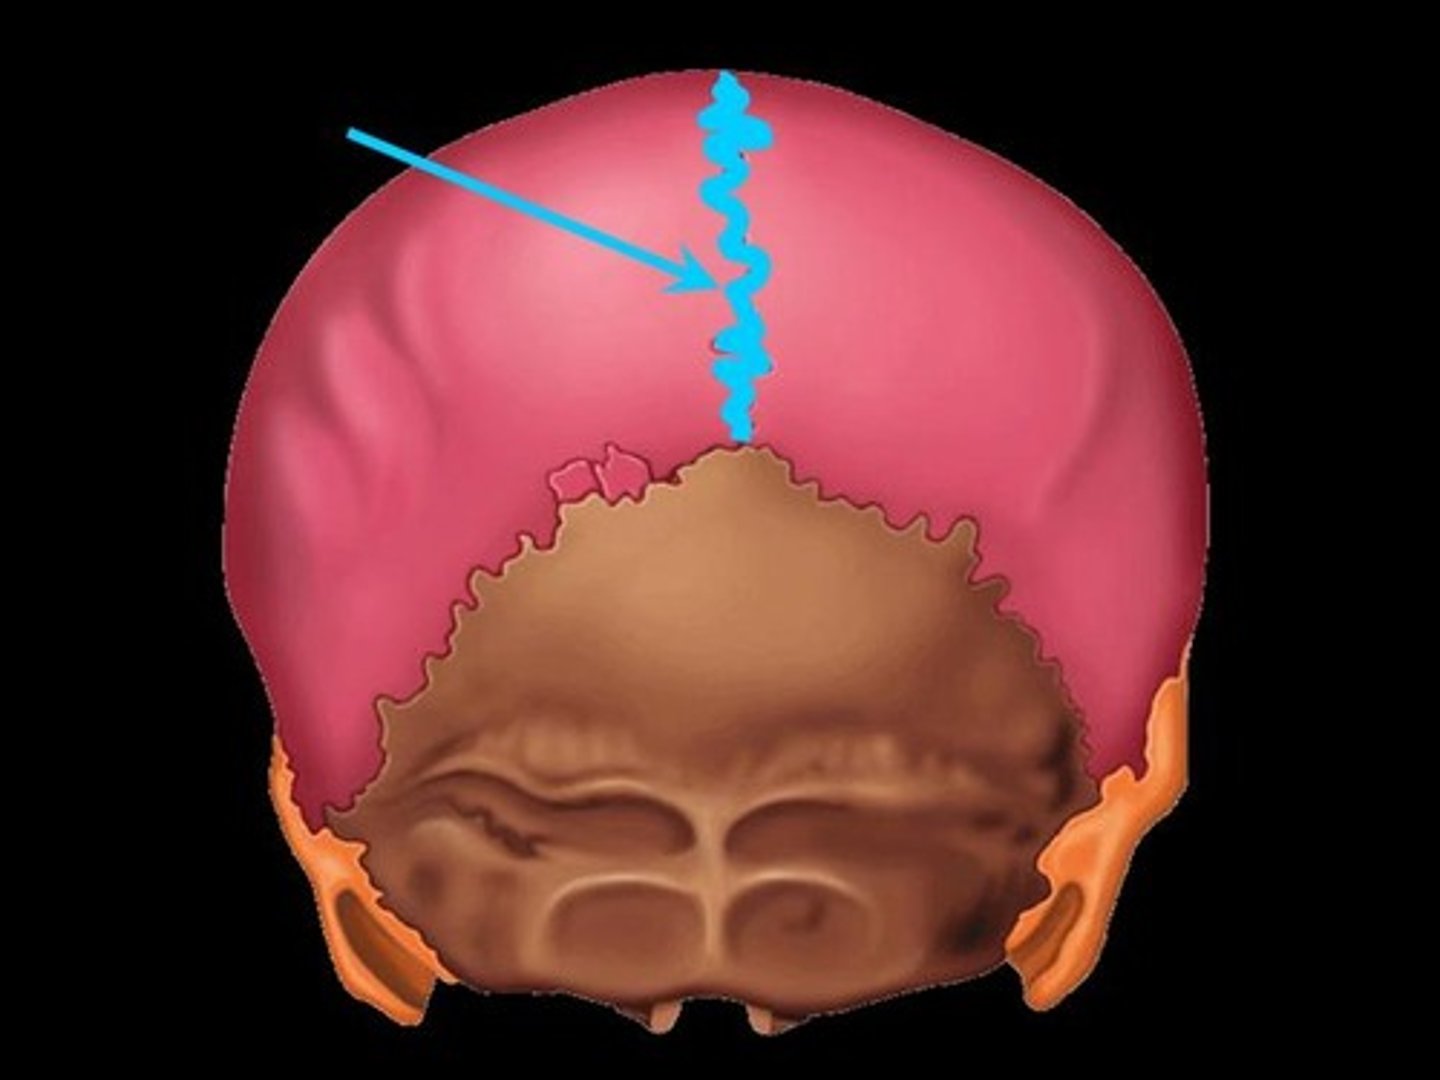

sagittal suture